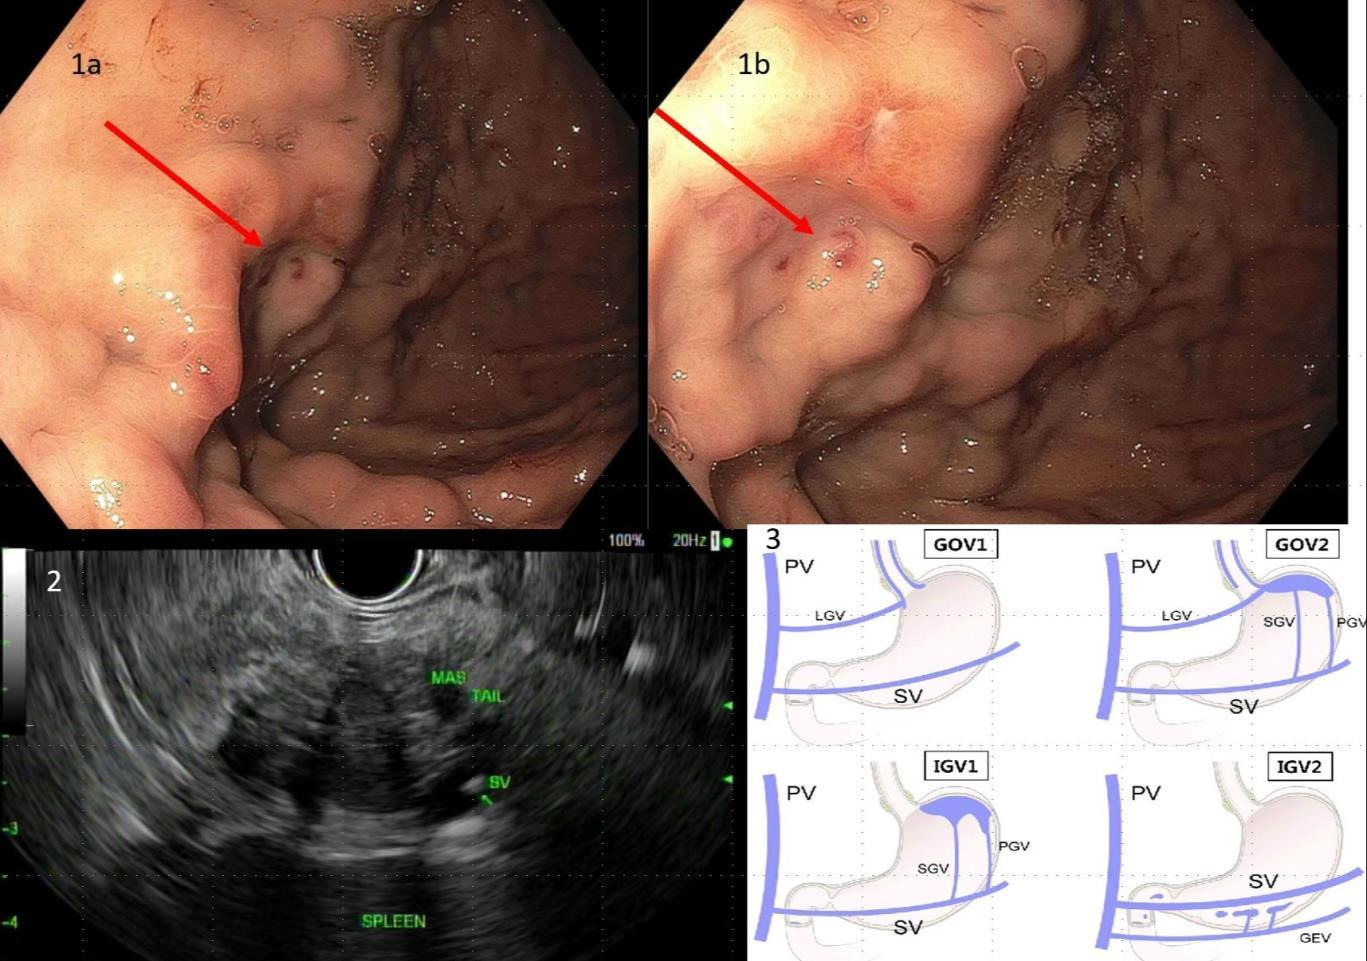

BURKITT LYMPHOMA INDUCED PSEUDOACHALASIA WITH DRAMATIC SYMPTOMATIC IMPROVEMENT POST-CHEMOTHERAPY

68

Marni H. Wilkoff1 , Emily S. Seltzer1 , Allison E. Wang1,2 , Bruno Almeida Costa1 , Bruce Gelman1

1Mount Sinai Morningside-West Hospitals, Icahn School of Medicine at Mount Sinai, New York, NY, United States;

2Mount Sinai Beth Israel Hospital, Icahn School of Medicine at Mount Sinai, New York, NY, United States 69